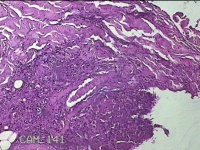

右侧颈部包块

性别

男

年龄

32岁

临床诊断

皮下结节

一般病史

发现右侧颈部包块3年余。

标本名称

大体所见

灰白暗红色包块1.5x1.3x0.7cm,表面光滑,切面灰白暗红色,质软。

图1

良性病变。